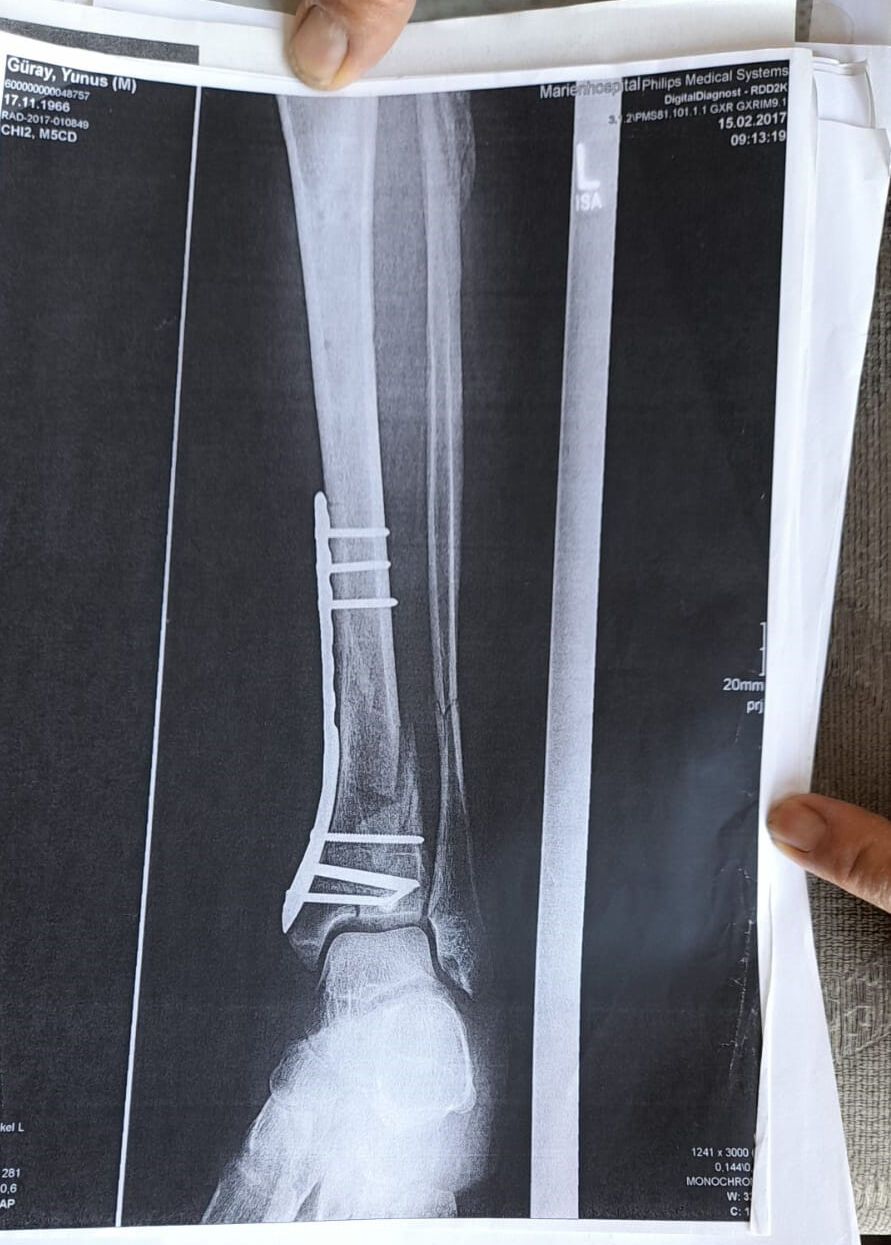

"Ömrümü yediler, demir var ayağımda, sakat bıraktılar. Ayağı keseceklerdi neredeyse. Şu an kalıcı sakatlık var. 1 sene kendime gelemedim, 2 haftada bir ameliyata giriyordum. Almanya'da 3 ay hastanede kaldım ve ayağımda yüzde 3'lük engel oluştu"

dedi.